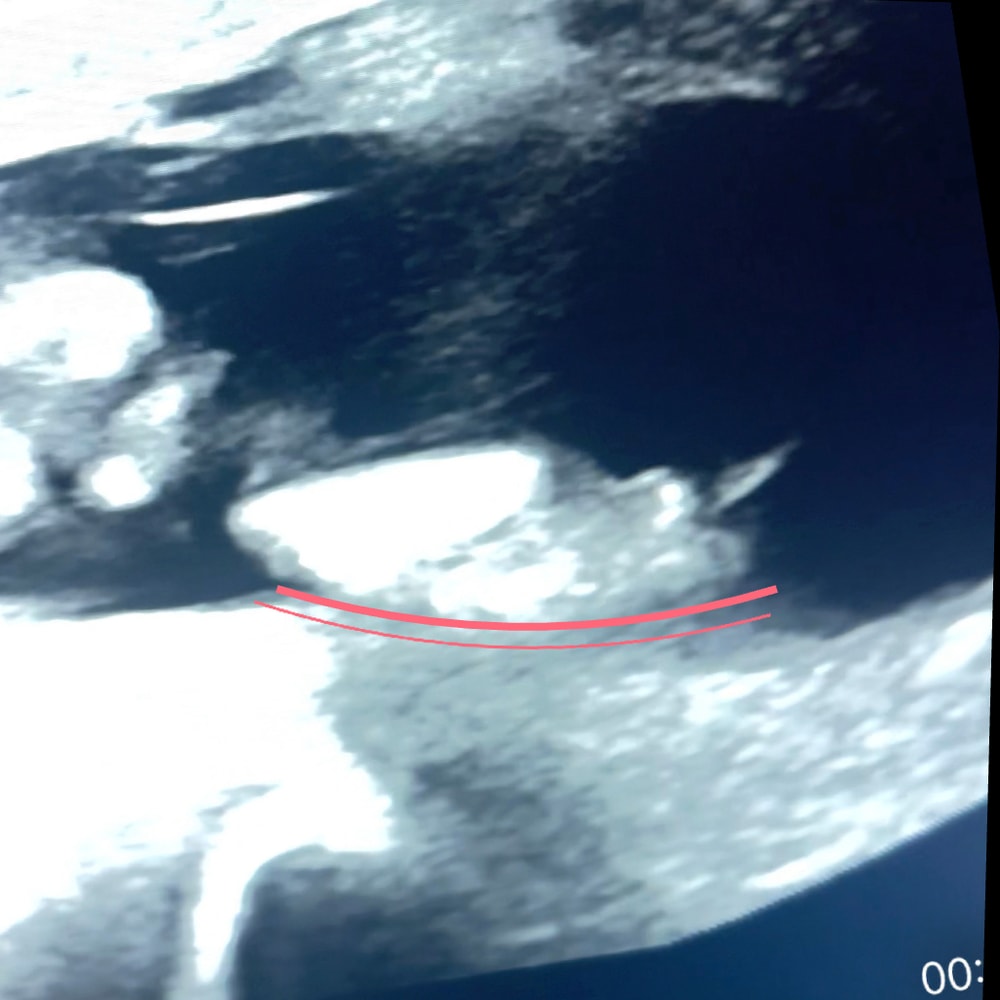

Девочки ,а кто понимает ?Помогите определить по половому бугорку

Пол малыша

Ну может предположительно кто как считаете ?)